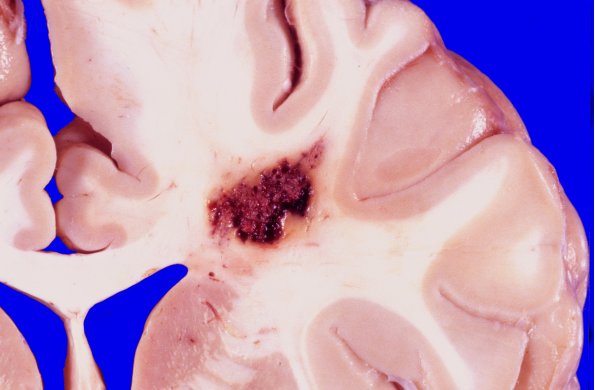

32A1 Cavernous angioma  (Case 32) gross 1

Adult patient with a large incidental cavernous malformation.